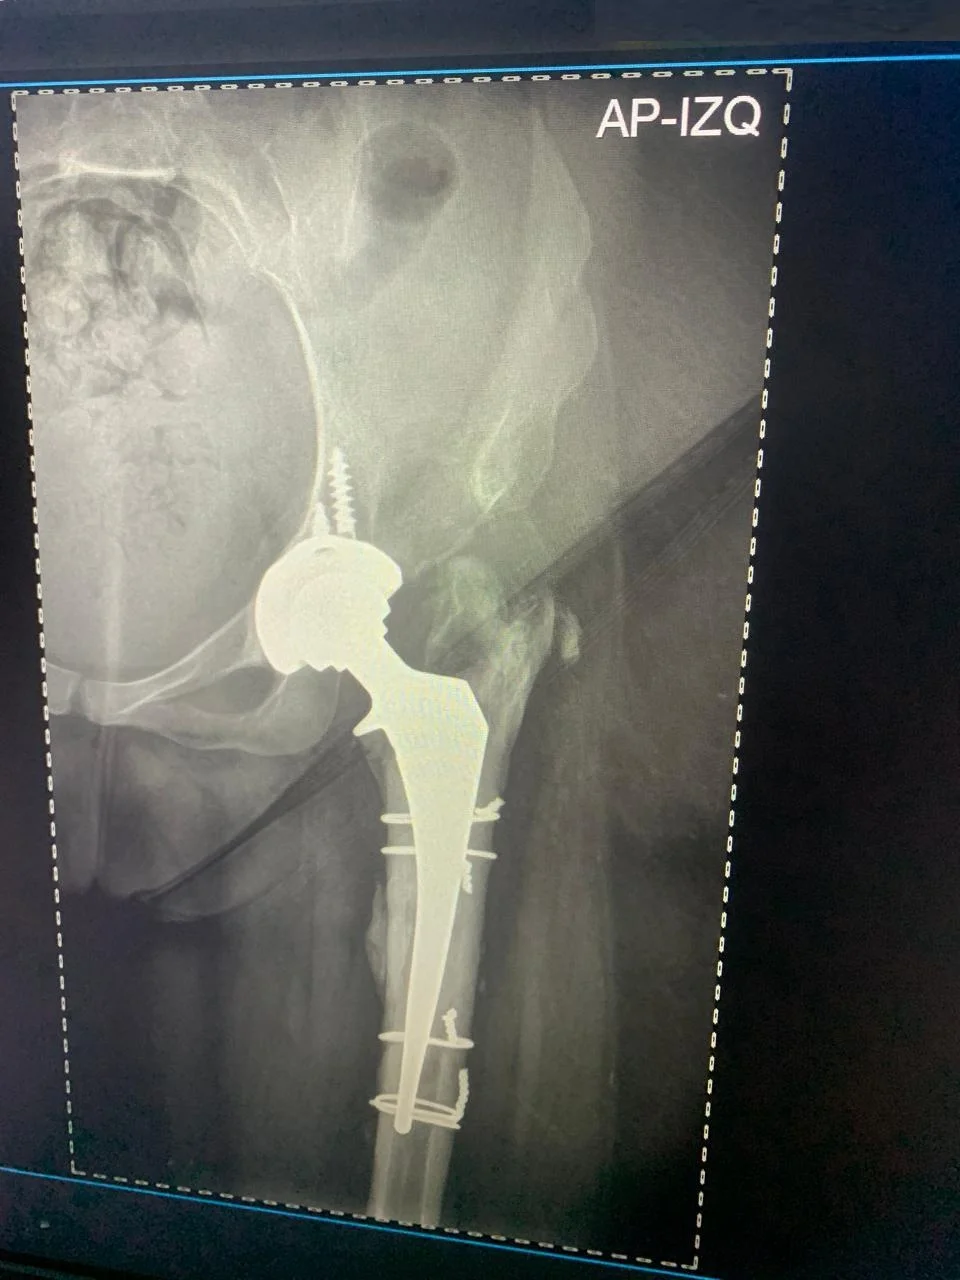

Después Radiografía postoperatoria de reemplazo total de cadera derecha exitoso - Dra. Ana Luz Bernabe

Reemplazo Articular

Artroplastia Total

de Cadera Derecha

• Perfil del Paciente: Femenino, 29 años. Cuadro de dolor severo de larga evolución.

• Diagnóstico: Limitación funcional severa para la marcha y actividades de la vida diaria.

• Procedimiento: Reemplazo total de cadera izquierda.

• Evolución (3 años): Reintegración total a sus actividades con excelente estabilidad y ausencia de dolor.